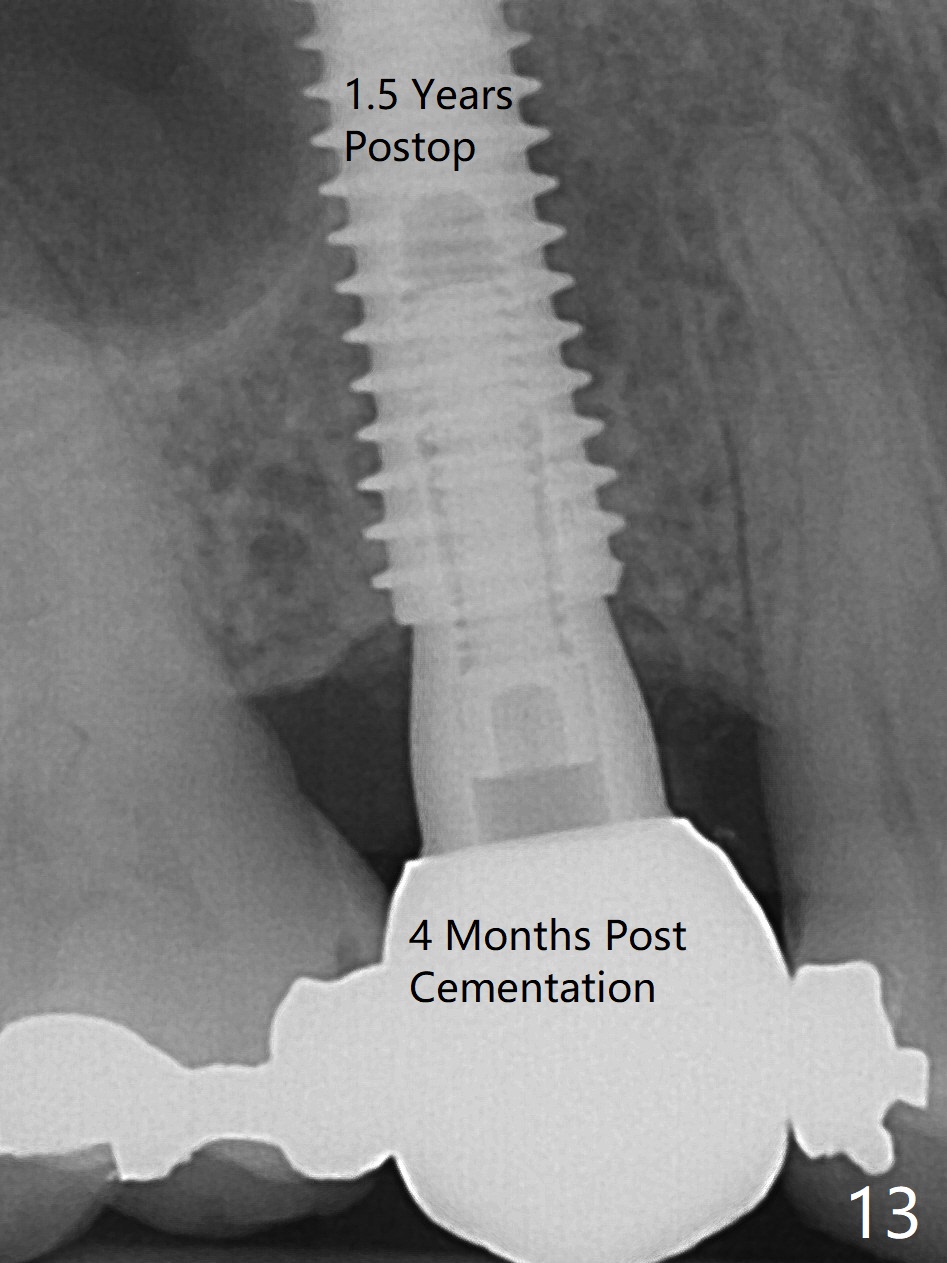

The 48-year-old man agrees to extract the tooth #4 with buccal and palatal fistulae (Fig.1,2 >) and large PARL (Fig.3 *) because of purulent discharge. The large post (Fig.3 P) is most likely associated with a longitudinal fracture. The latter is not noted until postop (Fig.4 <). Intraop finding is large amount of granulation tissue removed from the mesial apical region (Fig.3,5 *). With 10.5 mm offset, Sinus Approach Drill (19 mm) is estimated too short for sinus lift after 3x8.5 mm drill. Without careful repeated check, 2.2x10 and 2.2x11.5 mm drills are used. The sinus floor is perforated, but the membrane seems to be intact. The perforation is too small to insert PRF, but alright for allograft. Then nose blowing test shows that the sinus membrane is perforated, which seems to be repaired after placement of 2 pieces of PRF membrane, followed by another round of allograft (Fig.5 G), which is lifted by a 4x10 mm IS dummy implant. Before placement of a 4.5x11.5 mm final UF implant, allograft is placed in the 3 defective bony areas mentioned above, including the apical mesial one (Fig.6 *). But the final UF implant seems too short with non-satisfactory torque. The latter appears to be solved with the increased length of the implant (Fig.7). The gingiva around the provisional (P) is healthy without fistulae buccal (Fig.8) or palatal 17 days postop (Fig.9). A new abutment with 1 mm longer cuff is seated completely 5.5 months postop (Fig.10 < (no gap), as compared to Fig.7). The lower portion of the mesial defect seems to have been repaired (Fig.11 arrow, as compared to Fig.7). The bone in the sinus seems stable 1.5 years postop (Fig.12). There is no crestal bone loss 4 months post cementation (Fig.13). Return to Upper Premolar Immediate Implant, Trajectory II Xin Wei, DDS, PhD, MS 1st edition 09/27/2019, last revision 04/12/2021